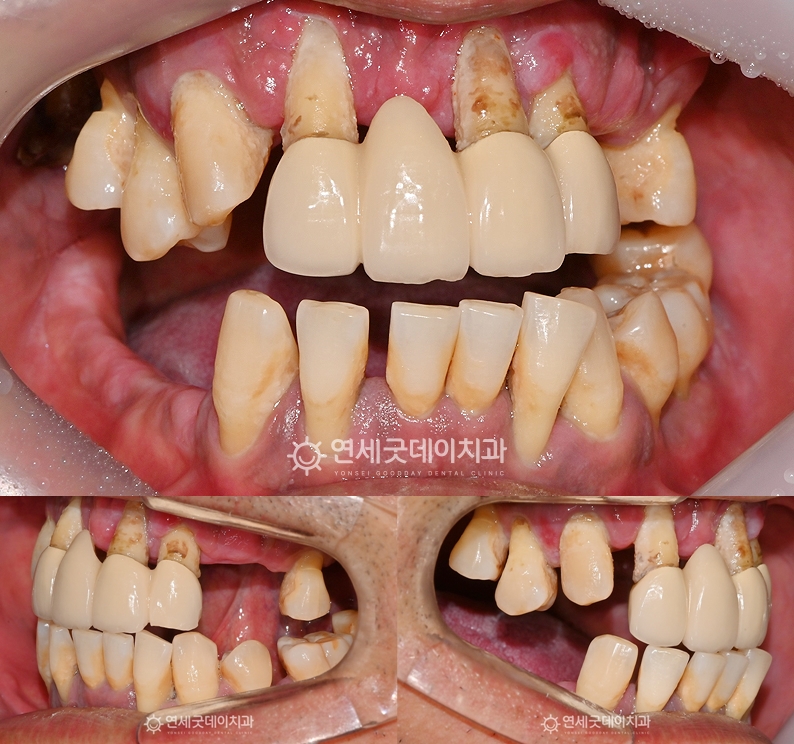

환자분은 중등도 이상의 치주질환으로 인해 이로 인해 치아 배열이 불규칙해지고

엑스레이 상에서도 상하악 모두 이 밖에도 좌우 어금니가 상실되었고

앞니 일부는 크라운으로 수복된 상태였으며 또한 잔존치의 예후도 좋지 않았기 때문에

수술 당일에 브릿지 임플란트 임시치아까지 환자분은 전악임플란트 치료이지만 모든 부위에

특히 길어보였던 전치부 잇몸 라인을 보완하며 또한 어금니 교합도 안정적으로 형성되었으며